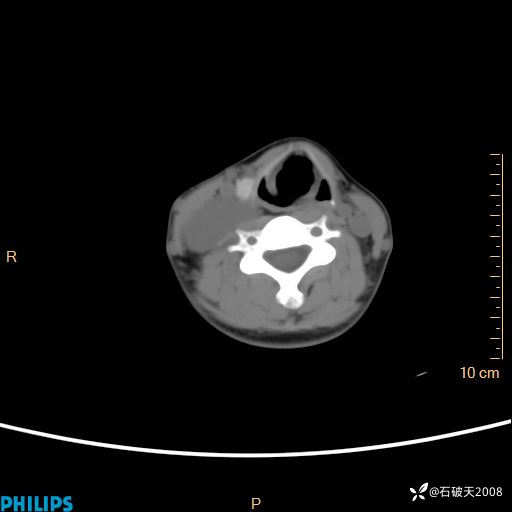

平扫